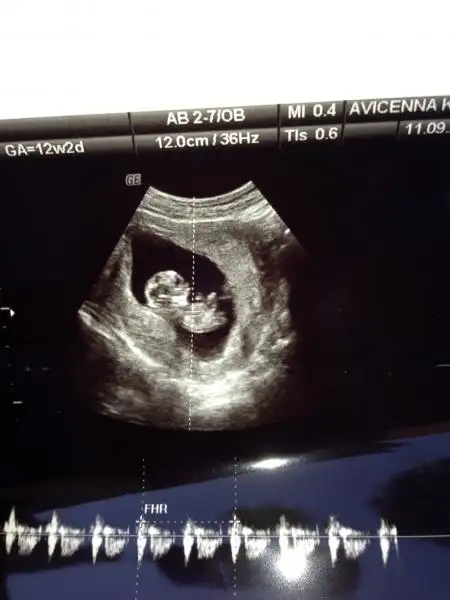

Cnm cok net gorunmuyo.yaklastirinca da bulanik ama gordugum ve anlayabildigim kadariyla erkek gibi sanki.

Resim çok kucuk yanılma payıyla birlikte ben erkek diyorum Hayırlısı olsun.

Canım bebegın yan yatmış sanki o yüzden yorum yapamadım. ama bir çıkıntı gibi birsey var ayak kemiği fln değilse epey inceledim erkek diyorum canım (görünen çıkıntı nubsa tabi) Gönlündeki olsun canım.

Cnm bana da erkek gibi geldi.sanki benimkine benzeyen beyaz renkte o cikintiyi goruyorum.benimkine dr.erkek dedi ona dayanarak seninki de erkek bence.